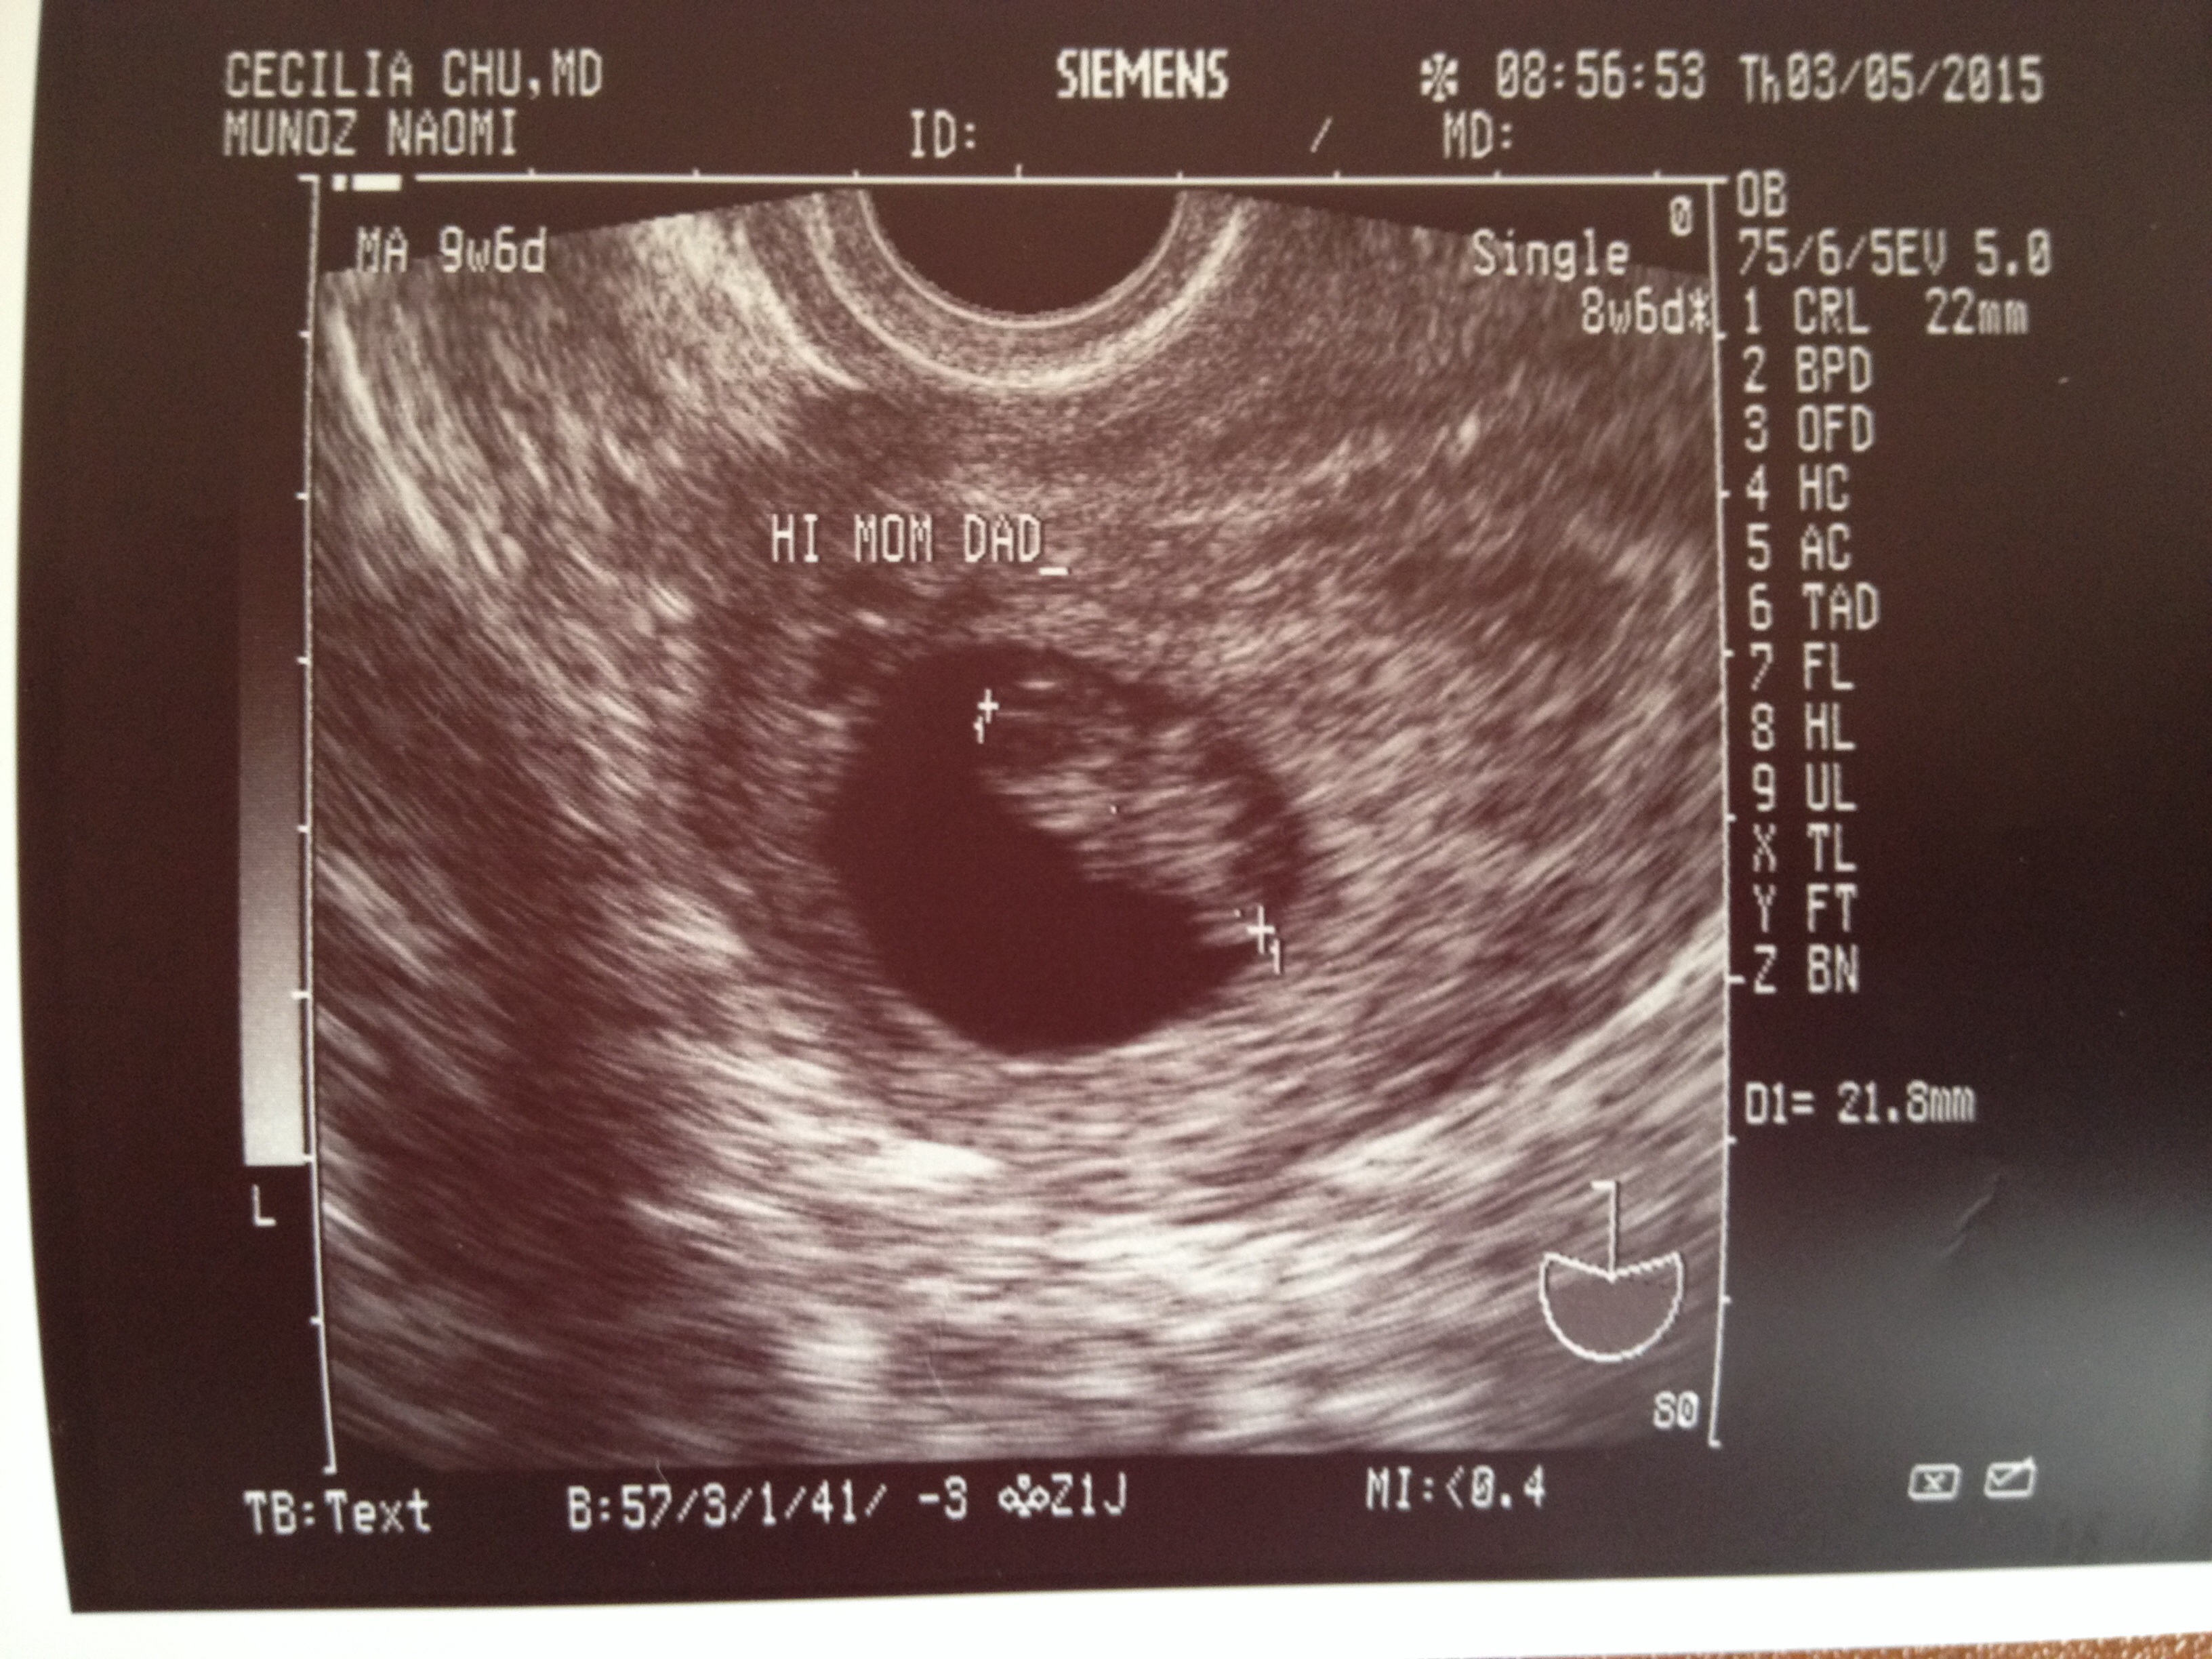

I wasn't going to post mine, but what the hell. Here is my little jellybean a week ago, at 8 weeks and 6 days. They gave me a regular-looking ultrasound picture and two of these freaky 3D ones.